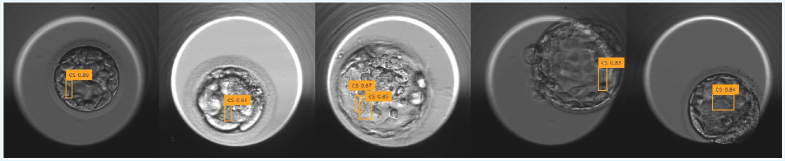

RF-DETR. RF-DETR consistently dominates all baselines. The medium, large, and base models achieve the highest scores across all IoU thresholds, including the strongest performance at mAP@25. Their refinement-based transformer design enables progressive feature aggregation, amplifying the weak spatial signatures of CS. The strong performance at high IoU (mAP@75) further highlights their superior ability to produce tight, spatially consistent bounding boxes. Qualitative examples of RF-DETR predictions are shown in Fig. 8, illustrating the model’s ability to localize extremely thin CS filaments under low-contrast conditions.

Refer to caption

Figure 8: Qualitative CS localization results across test samples.